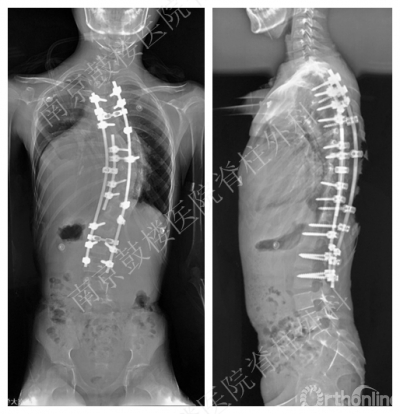

最终,该患儿在鼓楼医院脊柱外科及麻醉科团队的配合下顺利完成了手术,整个手术过程只能用惊心动魄来形容。患儿麻醉诱导十分顺利,但是术中还是出现了肺动脉危象,氧饱和度在15分钟内从100%掉到了60%,血压也是直线下降,心率高达180次/分,整个创面的渗血呈现暗紫色。好在在麻醉团队的各种支持调整下,生命体征逐渐恢复了稳定。整个手术时程在2小时内,出血量仅为600毫升,侧弯矫正达到70%以上。

患儿术后在ICU进行后续治疗,目前已从ICU转入脊柱外科病房继续无创呼吸治疗,现每天脱机能达1小时,已经能够独坐及站立,术后复查站立位全脊柱片提示矫形疗效满意,患儿再过几天就可以出院了。一家三口在3个多月的焦急等待及煎熬中终于露出了灿烂的笑容。

患儿术后全脊柱正侧位片